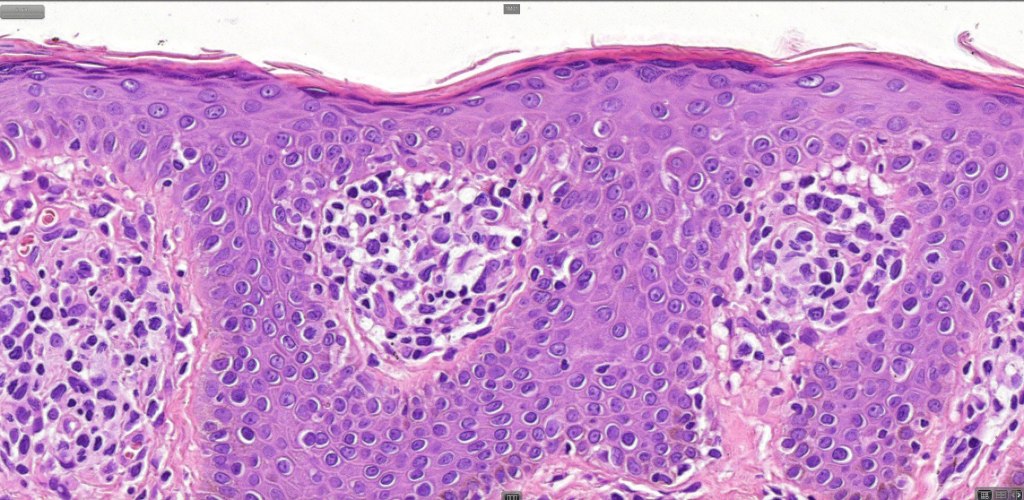

Histological features

•Variable histological features ranging from a non-specific superficial perivascular or band-like dermal infiltrate with minimal or no epidermotropism through to mycosis fungoides-like histology; can mimic atopic dermatitis

•Sézary cells are CD45RO, CLA, CD158 & CD4+